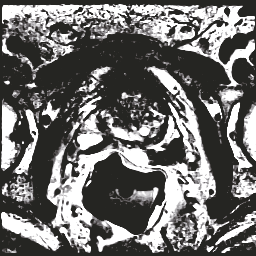

In this paper, we focus on three problems in deep learning based medical image segmentation. Firstly, U-net, as a popular model for medical image segmentation, is difficult to train when convolutional layers increase even though a deeper network usually has a better generalization ability because of more learnable parameters. Secondly, the exponential ReLU (ELU), as an alternative of ReLU, is not much different from ReLU when the network of interest gets deep. Thirdly, the Dice loss, as one of the pervasive loss functions for medical image segmentation, is not effective when the prediction is close to ground truth and will cause oscillation during training. To address the aforementioned three problems, we propose and validate a deeper network that can fit medical image datasets that are usually small in the sample size. Meanwhile, we propose a new loss function to accelerate the learning process and a combination of different activation functions to improve the network performance. Our experimental results suggest that our network is comparable or superior to state-of-the-art methods.